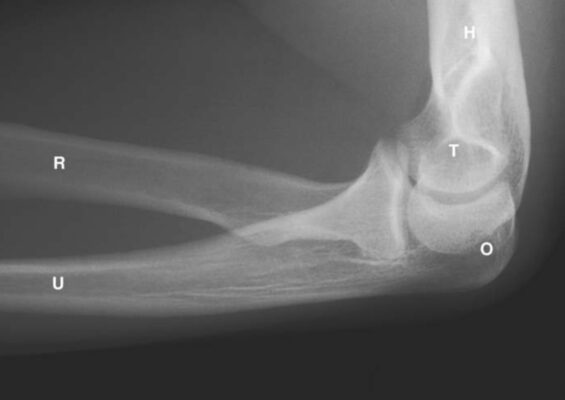

LIÊN HỆ X QUANG KHỚP KHUỶU

Ghi chú:

- H = Humerus; xương cánh tay

- O = Olecranon process of ulna; mỏm khuỷu xương trụ

- R = Radius; xương quay

- U = Ulna; xương trụ

- T = Trochlea of humerus; ròng rọc xương cánh tay

- M = Medial epicondyle of humerus; lồi cầu trong xương cánh tay

- C = Capitellum of humerus; chỏm con xương cánh tay

ÔN LẠI: